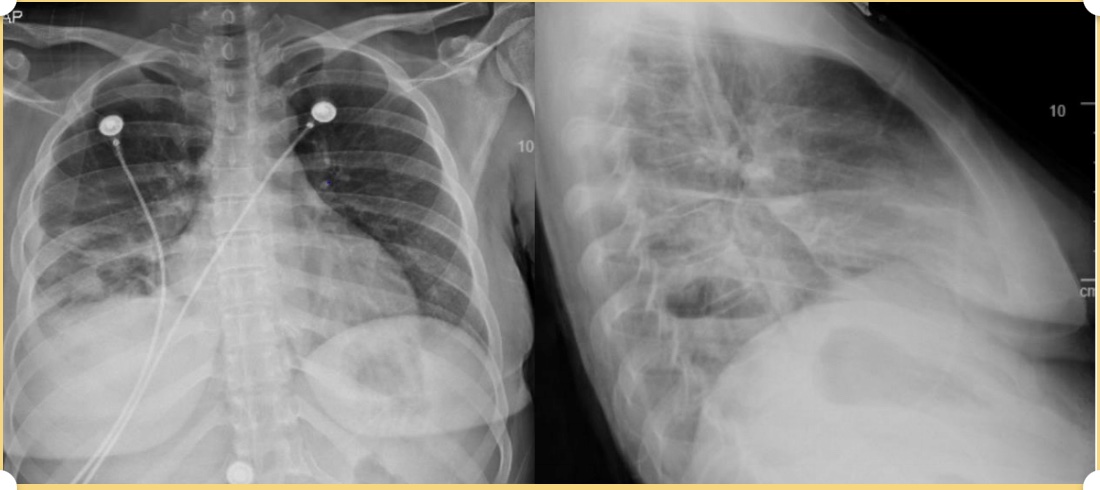

A 30 yo female with a hx of IVDA presents with 2 weeks of progressively worsening right sided pleuritic chest pain, productive cough and shortness of breath. She reports five days of nausea, vomiting and diarrhea as well. A chest x-ray is shown. What's the diagnosis? Scroll down for answer.

Answer: Cavitary lesion with air-fluid level consistent with abscess from septic emboli secondary to infective endocarditis